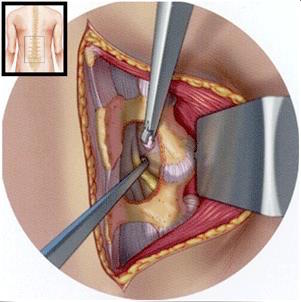

Básicamente en llegar a la zona dónde está la hernia y el nervio comprimido por ella, liberar éste y sacar la hernia que provoca la compresión.

Hay varias técnicas quirúrgicas y con resultados similares, las más utilizadas la discectomía y la microdiscectomía.